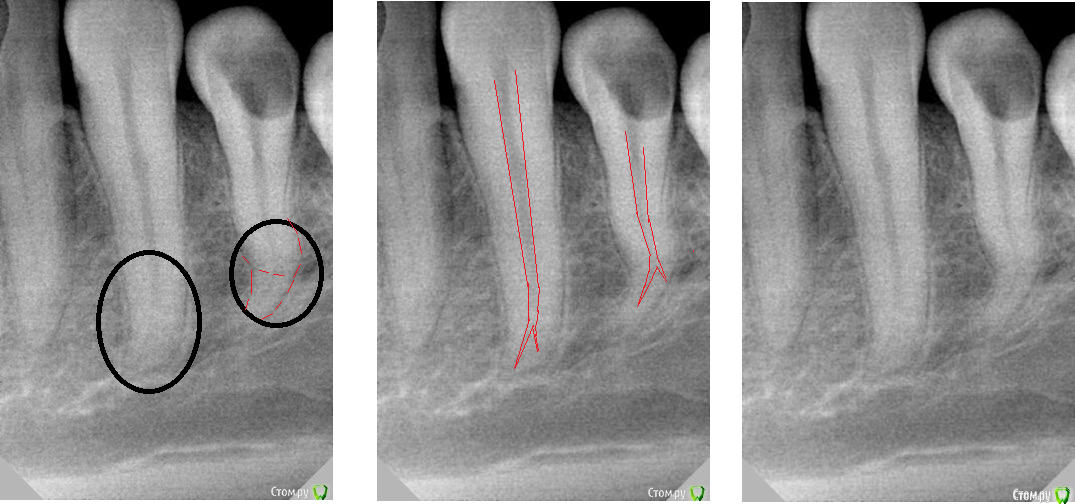

Ker Опубликовано 1 апреля, 2016 Поделиться Опубликовано 1 апреля, 2016 (изменено) Думаю что там два канала.Но может и ошибаюсь. Изменено 1 апреля, 2016 пользователем Ker 2 Ссылка на комментарий

Нюрок Опубликовано 4 апреля, 2016 Поделиться Опубликовано 4 апреля, 2016 Думаю что там два канала.Но может и ошибаюсь.тоже вижу здесь два корня Ссылка на комментарий

Гарриевич Опубликовано 5 апреля, 2016 Поделиться Опубликовано 5 апреля, 2016 алгоритм такойберете большой файл, если работаете ротари, то 35/06 или приблизительно такой, и разрабатываете да первого изгиба, затем на один размер и меньший конус 04 файл до второго изгиба, затем на размер больше, того же 04 конуса. Затем на два размера меньше 04 конуса. думаю к этому моменту дойдете до нужной длины, затем 10 к-файл определить длины канала, отступить 1 мм и работатьудачного разрешения случая 2 Ссылка на комментарий